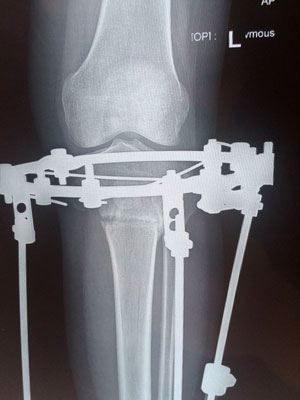

Исходник - 34 года.

Дата операции 29.09.2017г.

2-я ротация.